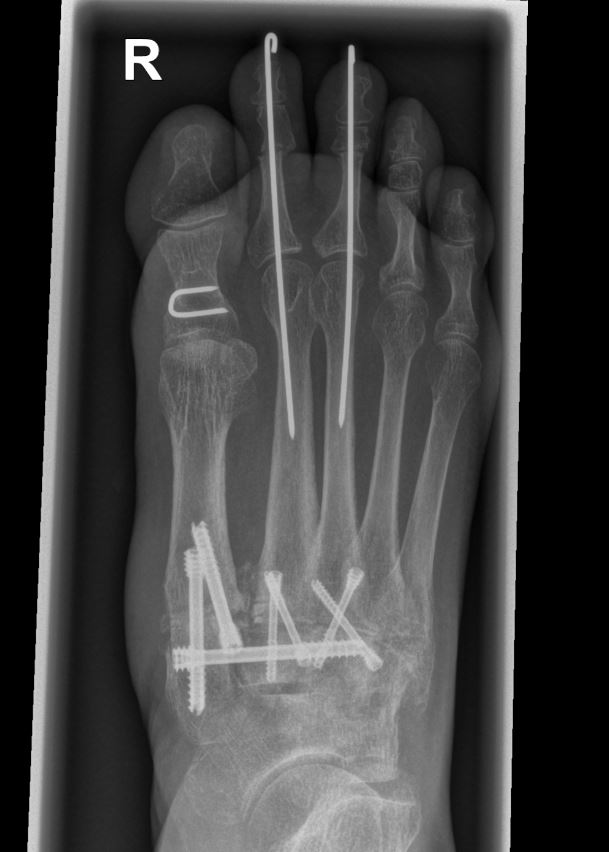

• Temporäre Fixierung mit 1,6 K-Drähten, BV- Kontrolle. Bei korrekter Stellung definitive Osteosynthese entweder mit je 2 Kompressionsschrauben, Platten oder Klammern.

• Die mechanisch stabilste Situation ist mit dorsalen winkelstabilen Platten, optional mit Kompressionsschraube zu erreichen 3.

• BV-Kontrolle von Stellung der Knochen und der Lage des Osteosynthesematerials.

• Röntgenkontrolle nach 8-10 Wochen, dann - je nach knöchernem Durchbau - Übergang zur Vollbelastung im Konfektionsschuh (Abb. 24 und 25).

Beispiel Lisfranc Arthrodese bei posttraumatischer Arthrose

Zum Lesen der Bildbeschreibung und zur Vollansicht bitte die Bilder anklicken. Bilder: C. Hase